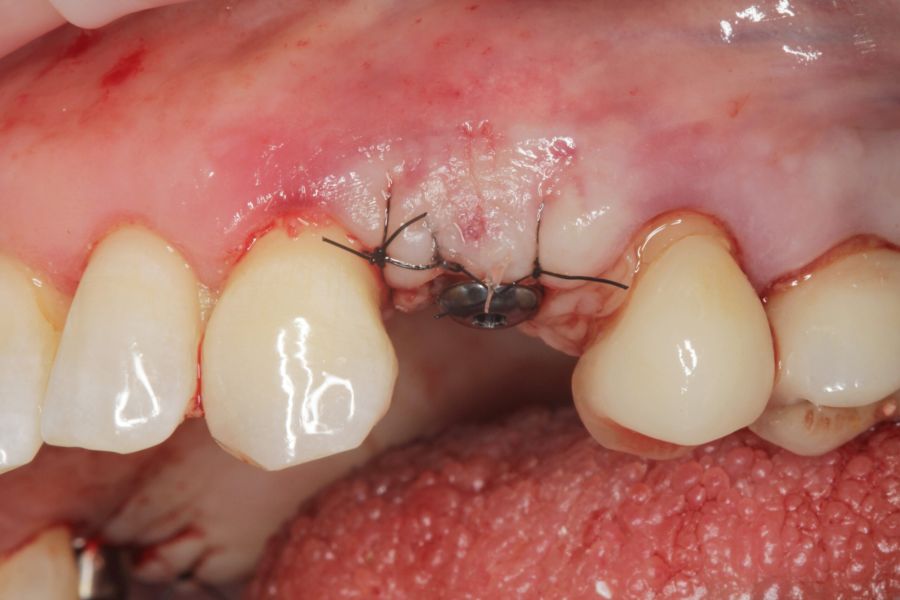

Los pacientes acudieron cada 6 meses a la realización de radiografías panorámicas y periapicales de control y sobre estas radiografías y se realizaron las mediciones necesarias para comprobar la estabilidad y pérdida ósea crestal de los implantes. Una vez obtenida la radiografía en formato digital fue calibrada mediante un software específico (Sidexis measure y Digora) a través de una longitud conocida en la radiografía como es el implante dental. Una vez introducimos la medida de calibración, el programa informático realizó un cálculo basado en esta medida para eliminar la magnificación, pudiendo realizar mediciones lineales exentas de este error. La pérdida ósea marginal se definió como la distancia entre el hombro del implante y el primer punto de contacto óseo visible sobre su superficie. En estas visitas se realiza además sondaje de los implantes y se anotaron los posibles signos y síntomas de periimplantitis o mucositis (sangrado espontáneo, al sondaje, inflamación o supuración).

En cuanto a la rehabilitación protésica, en todos los casos se utilizó una prótesis atornillada con transepitelial para prótesis unitaria. La supervivencia de las prótesis fue del 100%, sin encontrarse fracaso en ninguna de ellas al igual que los implantes, con un tiempo de seguimiento de tres años. Durante el primer año, en las visitas de control, ninguno de los implantes mostró sangrado al sondaje ni inflamación de los tejidos periimplantarios. La media de la pérdida ósea en este punto fue de 0,32 mm (+/- 0,60) y la media de la pérdida ósea distal de 0,31 (+/- 0,48). A los dos años, no se registraron tampoco signos inflamatorios en ninguno de los implantes y la pérdida ósea mesial del conjunto fue de media de 0,38 mm (+- 0,54) y la distal de 0,64 mm (+/- 0,70). En la última visita a los 3 años, los tejidos periimplantarios siguieron estables, sin signos de inflamación y la media de la pérdida ósea mesial fue de 0,40 mm (+/- 0,53) y la distal de 0,69 (+/- 0,55) (Figura 5). En las Figuras 6-12 se muestra uno de los casos incluidos en el estudio.